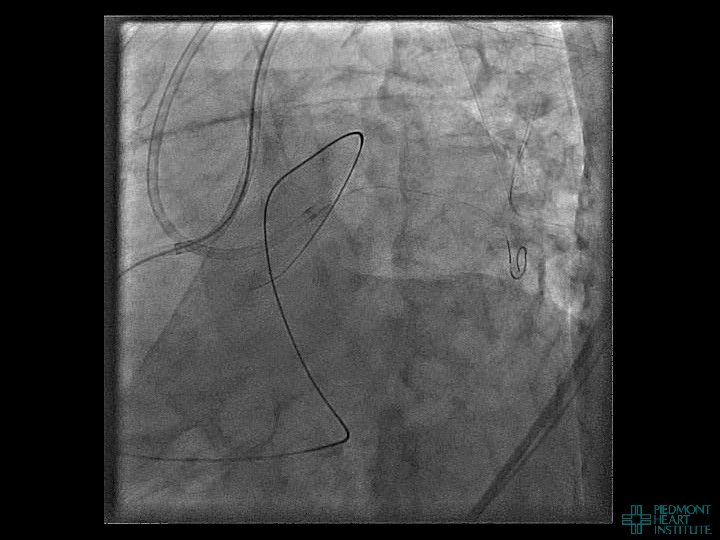

Coronary Perforation Methods of Patient Management • Dual Catheter (‘Ping Pong’) Technique • Prolonged

Coronary Perforation Methods of Patient Management • Dual Catheter (‘Ping Pong’) Technique • Prolonged balloon inflation and covered stents • Reversal of anticoagulation — Know contradictions to protamine sulfate for UFH; Avoid bivalirudin, LMWH — Reserve GP 2 b 3 a inhibition until successful crossing and wire change-out Embolization • — Coil, gelfoam, methacrylate, autologous blood/fat • Microcatheter Occlusion • Confirmation of successful management — Contralateral injection — Right heart catheterization — Echocardiogram — Contrast echocardiography